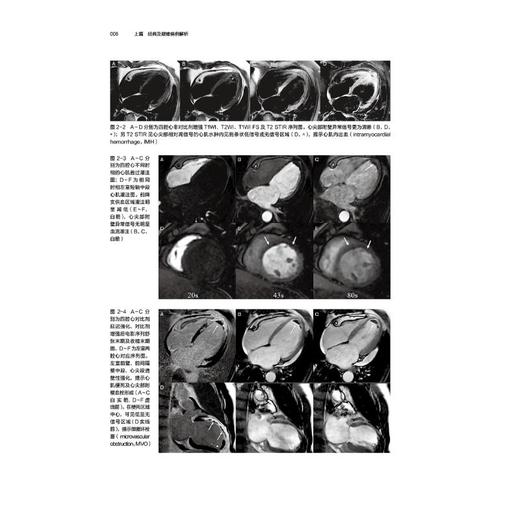

病例1冠心病,急性心肌梗死

病例2冠心病,急性心肌梗死(微循环障碍)